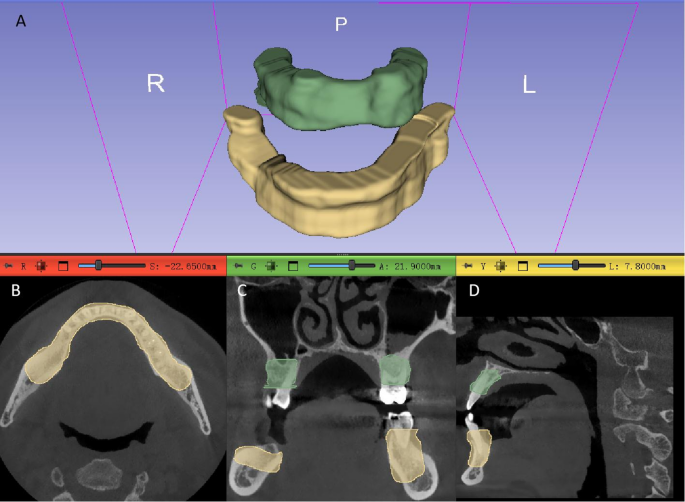

The mandibular and maxillary regions were segmented and subsequently merged into a single region of interest (ROI). This process was performed using 3D Slicer software(www.slicer.org, version 5.6.2) by an oral and maxillofacial specialist with 10 years of experience. Region of Interest (ROI) Definition for Periodontal Analysis: Maxilla: The upper boundary is defined by the line connecting the lower wall of the maxillary sinus and the floor of the nose to the lower wall of the contralateral maxillary sinus. The lower boundary is the line connecting all the enamel-cementum junctions of the teeth. Mandible: The upper boundary is the line connecting all the enamel-cementum junctions of the teeth. The lower boundary is defined by the line connecting the inferior alveolar canals bilaterally in the posterior region and the bilateral mental foramen in the anterior region. Multiplanar Reconstruction (MPR) Views (Axial, Sagittal, Coronal) for Both Maxilla and Mandible: The boundaries include the labial and buccal alveolar bone plates and the lingual or palatal bone plates(Fig. 1). The segmentation results were independently reviewed and any inaccuracies were corrected to ensure the highest quality of the delineated anatomical regions.

A schematic illustration from a Cone Beam Computed Tomography (CBCT) scan of a patient, highlighting the outlines of the periodontal tissues. A: 3D view of the regions of interest. B: Axial view of the CBCT. C: Coronal view of the CBCT. D: Sagittal view of the CBCT.